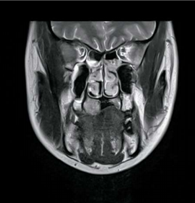

症例1

75歳男性。

疼痛などの自覚症状が無かったため、受診せずに放置。

そのため、ここまで大きくなってからの受診となりました。

参考画像